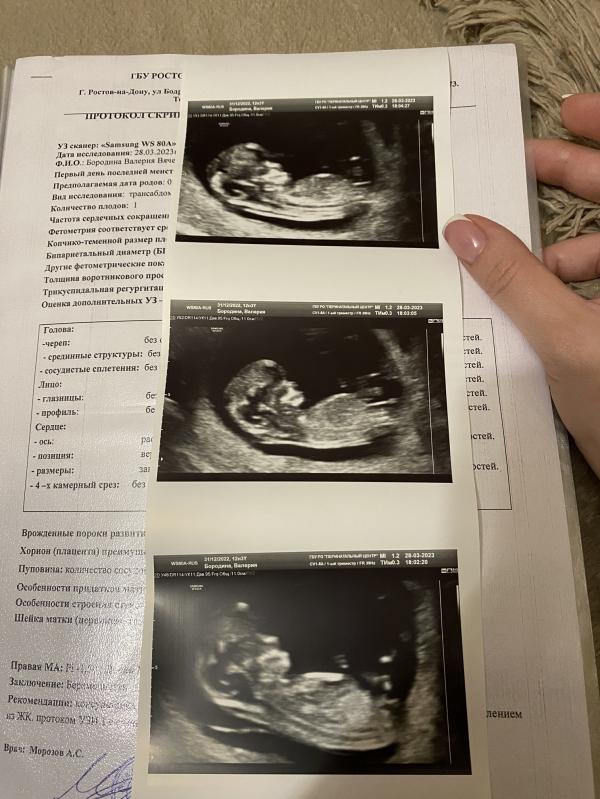

Для истории… первый скрининг…

Я так ждала этот скрининг , что наверное выдернула пару волос на голове. Почему-то мне было не по себе, я очень переживала что будет что-то не так. Думаю каждая девушка ощущает эти страхи и чувства перед первым знакомством с малышом. Мы приехали в ПЦ (муж с сыном были моей поддержкой) запись была на 17.15 в 15 кабинете у Морозова А.С. , очередь была большой , что больше усугубляло мое беспокойство , смотря на мужа , думаю тоже переживал, но не показывал . И вот нас позвали . Не помню как зашла, как легла , ну тут же как на экране показался образ моего чада, сразу стало как то спокойно и тепло на душе , дурные мысли ушли мимолетно. Врач внимательно все смотрел и измерял, рассказывал где и что , какие крошечные ручки и ножки . Вообщем я говорю посмотрите пол, долго рассматривал и в итоге …девочка… 80% ДЕВОЧКА!!!!!! Знаю что это не точно, знаю что часто ошибаются , но я почему то теперь 99% знаю что это моя дочурка ! Жду теперь с нетерпением результаты анализа крови. Но моей радости нет предела . Муж с первым ребёнком очень ждал девочку, даже в день операции спрашивал когда родила, девочка ???? А когда услышал со второго раза , что это скорее всего будет дочка , я его потеряла на два дня( в плане что он был сам не свой, ходил со своими мыслями в голове, переваривал все😂)

28.03.2023 …первый скрининг…